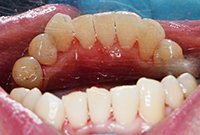

Снятие твердых зубных отложений ультразвуком

Удаление твердых зубных отложений ультразвуковой насадкой у девушки 27 лет.

Снятие твердых зубных отложений ультразвуком До

Снятие твердых зубных отложений ультразвуком После